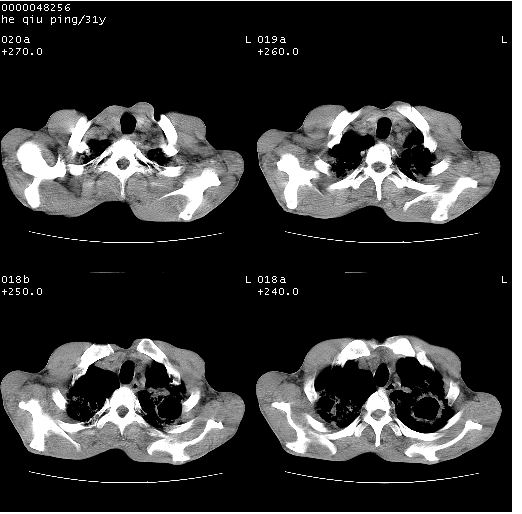

标题: CT13402:M,31Y。肺结核伴空洞形成? [打印本页]

标题: CT13402:M,31Y。肺结核伴空洞形成?

咳嗽半月余,消瘦体质,呼吸音弱。无其他病史。cr:肺转移瘤待。

双上肺多发空洞,双飞散在分布大小不一的片状结高密度影节状大片状高密度影。符合结合肉芽肿形成及空洞形成。

双侧弥漫性病变,双上叶尖后段、下叶北段见多个空洞,多见于结核感染。右中叶及双下叶斑片状,结节状影,考虑为肉芽肿形成及支气管播散。但由于患者消瘦体质,抵抗力低下,若继发感染,如金葡菌肺炎也有可能。

病灶多形性,有空洞形成。考虑肺结核伴空洞形成,两下肺支气管播散!